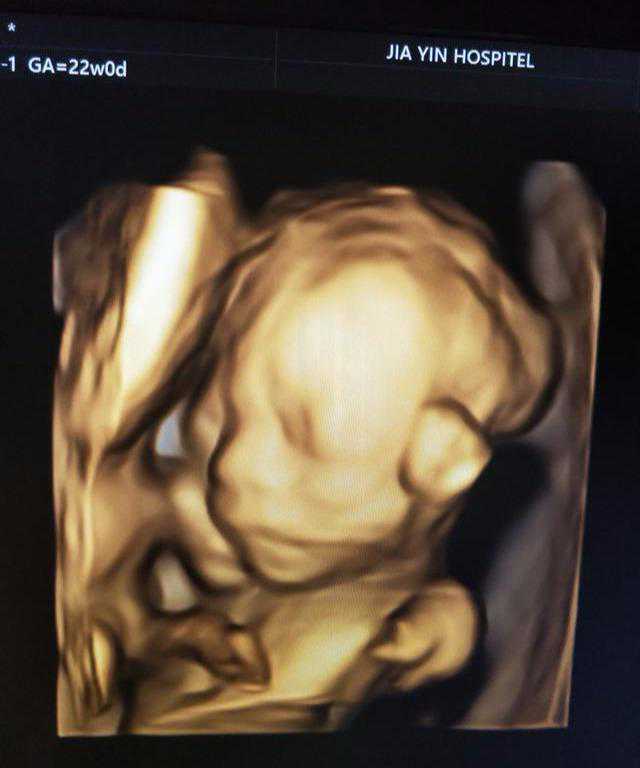

试管怀上宝宝,孕中期给大家一些实用经验

宝宝二十周加了。在宝宝十二周以前还很紧张,到最近一个多月好像...